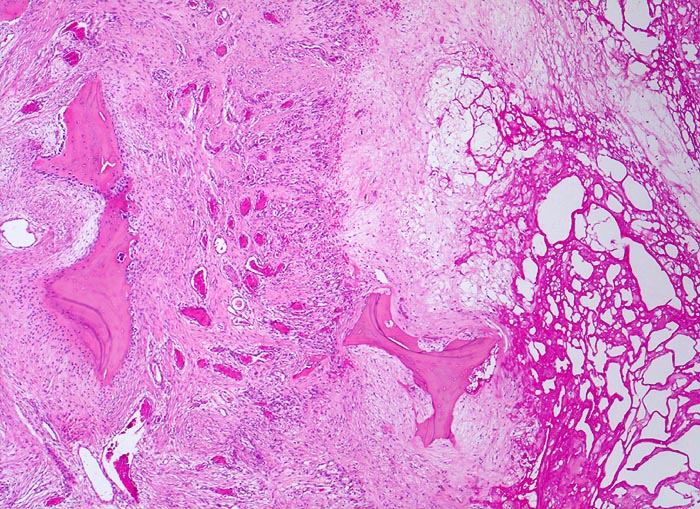

• Deformierte Gelenkfläche.

• Weitgehendes Fehlen des hyalinen Gelenkknorpels.

• Sekundäre Sklerose der freiliegenden Spongiosa mit Anbau von breiten Faser- und Lamellenknochensäumen an die alten Bälkchen.

• Herde von metaplastischem Faserknorpel in der Gelenkfläche.

• Randosteophyt, welcher über Resten des dort noch vorhandenen Gelenkknorpels entstanden ist (Verdoppelung des Knorpels).

• Nekrosebezirk in der Spongiosa (Geröllzyste) umgeben von einem Granulationsgewebssaum und Narbengewebe.